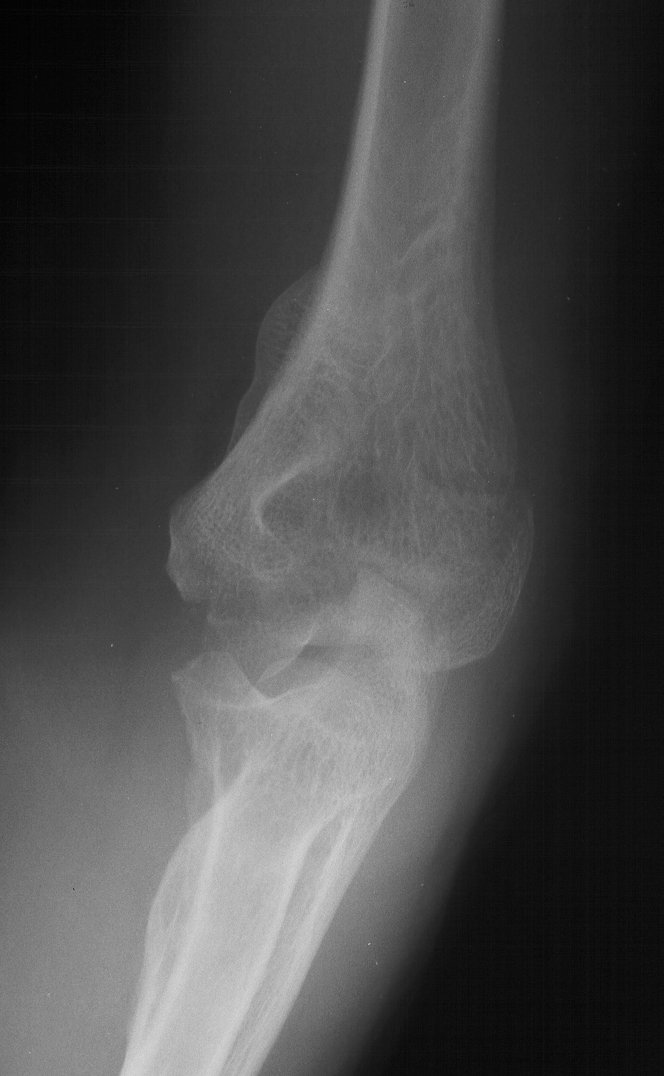

81 year old physically active woman sustained a left elbow fracture in a syncope related fall.

Lateral and central fracture component displacement.

Unusual contour visible at the medial metaphyseal flare.

This is seen on the lateral view to be the anterior half of the central articular surface.